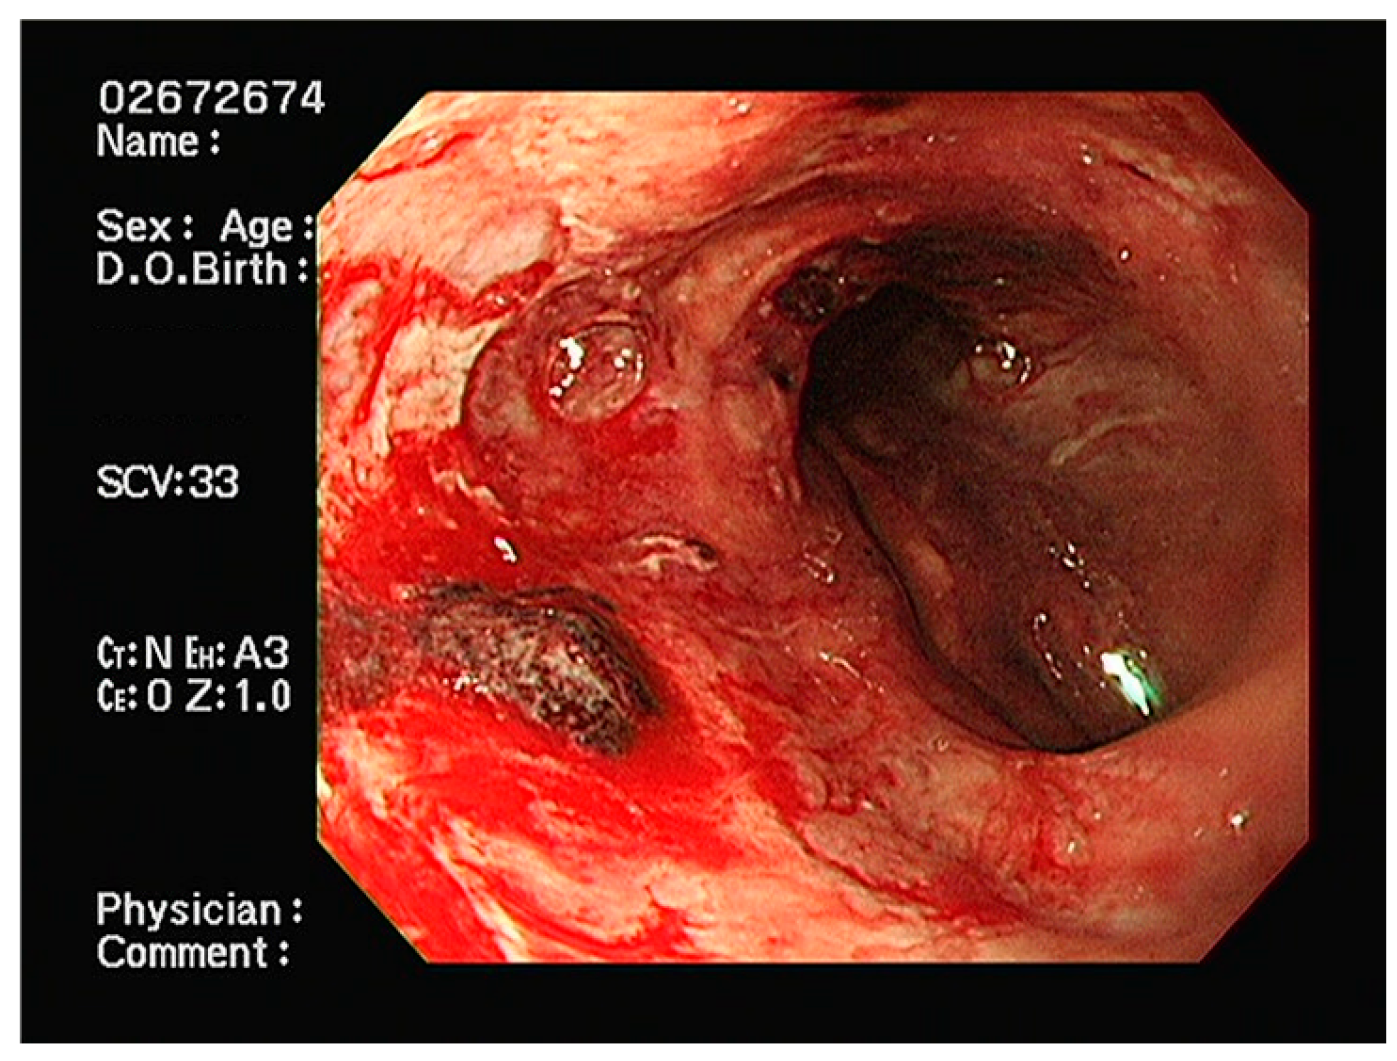

2. Case Presentation